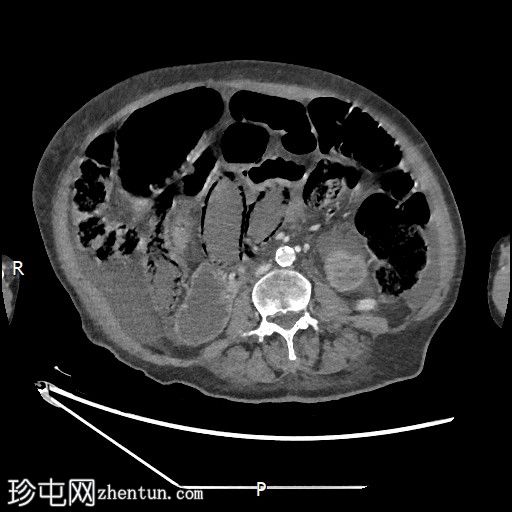

轴位平扫

大肠内可见中度粪便。横结肠轻度扩张(约6.6厘米)。

数处小肠袢直径接近临界值(约3厘米),部分肠袢内可见粪便。

腹部中央及右侧可见数处小肠袢肠壁明显变薄,并可见肠壁积气。

少量腹水。

主动脉及其内脏分支可见明显动脉粥样硬化。肠系膜上动脉(SMA)开口处中度至重度狭窄;但开口后显影良好。

目前未见明显的门静脉-肠系膜静脉积气。

无气腹。